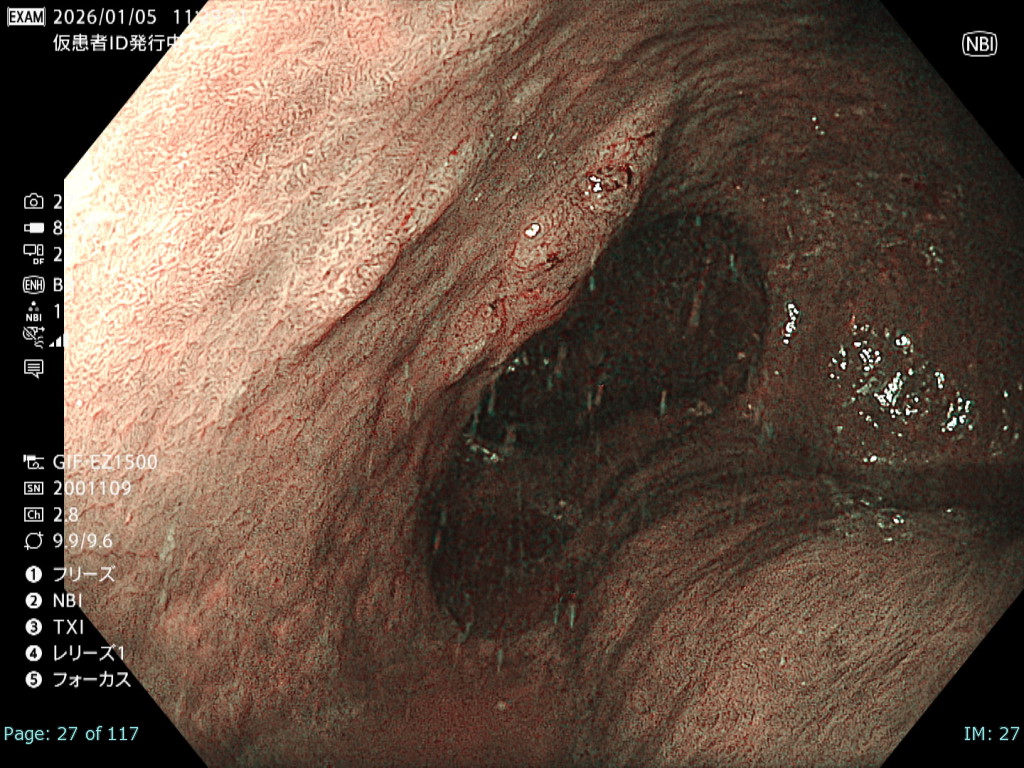

• NBI観察②(拡大)

強調設定:B8

図5

病変は易出血性で観察難易度が高く、NBI拡大観察では微小血管構築像は視認可能であるものの、出血の影響で一部で輪郭が不鮮明となった。

• NBI+TXI観察② (拡大)

切替前 NBI強調設定:B8

NBI+TXIレベル:中

図6

出血の影響を受ける条件下でも、NBI+TXI拡大観察は、NBI拡大観察と比較し、微小血管構築像がより明瞭になる印象だった。